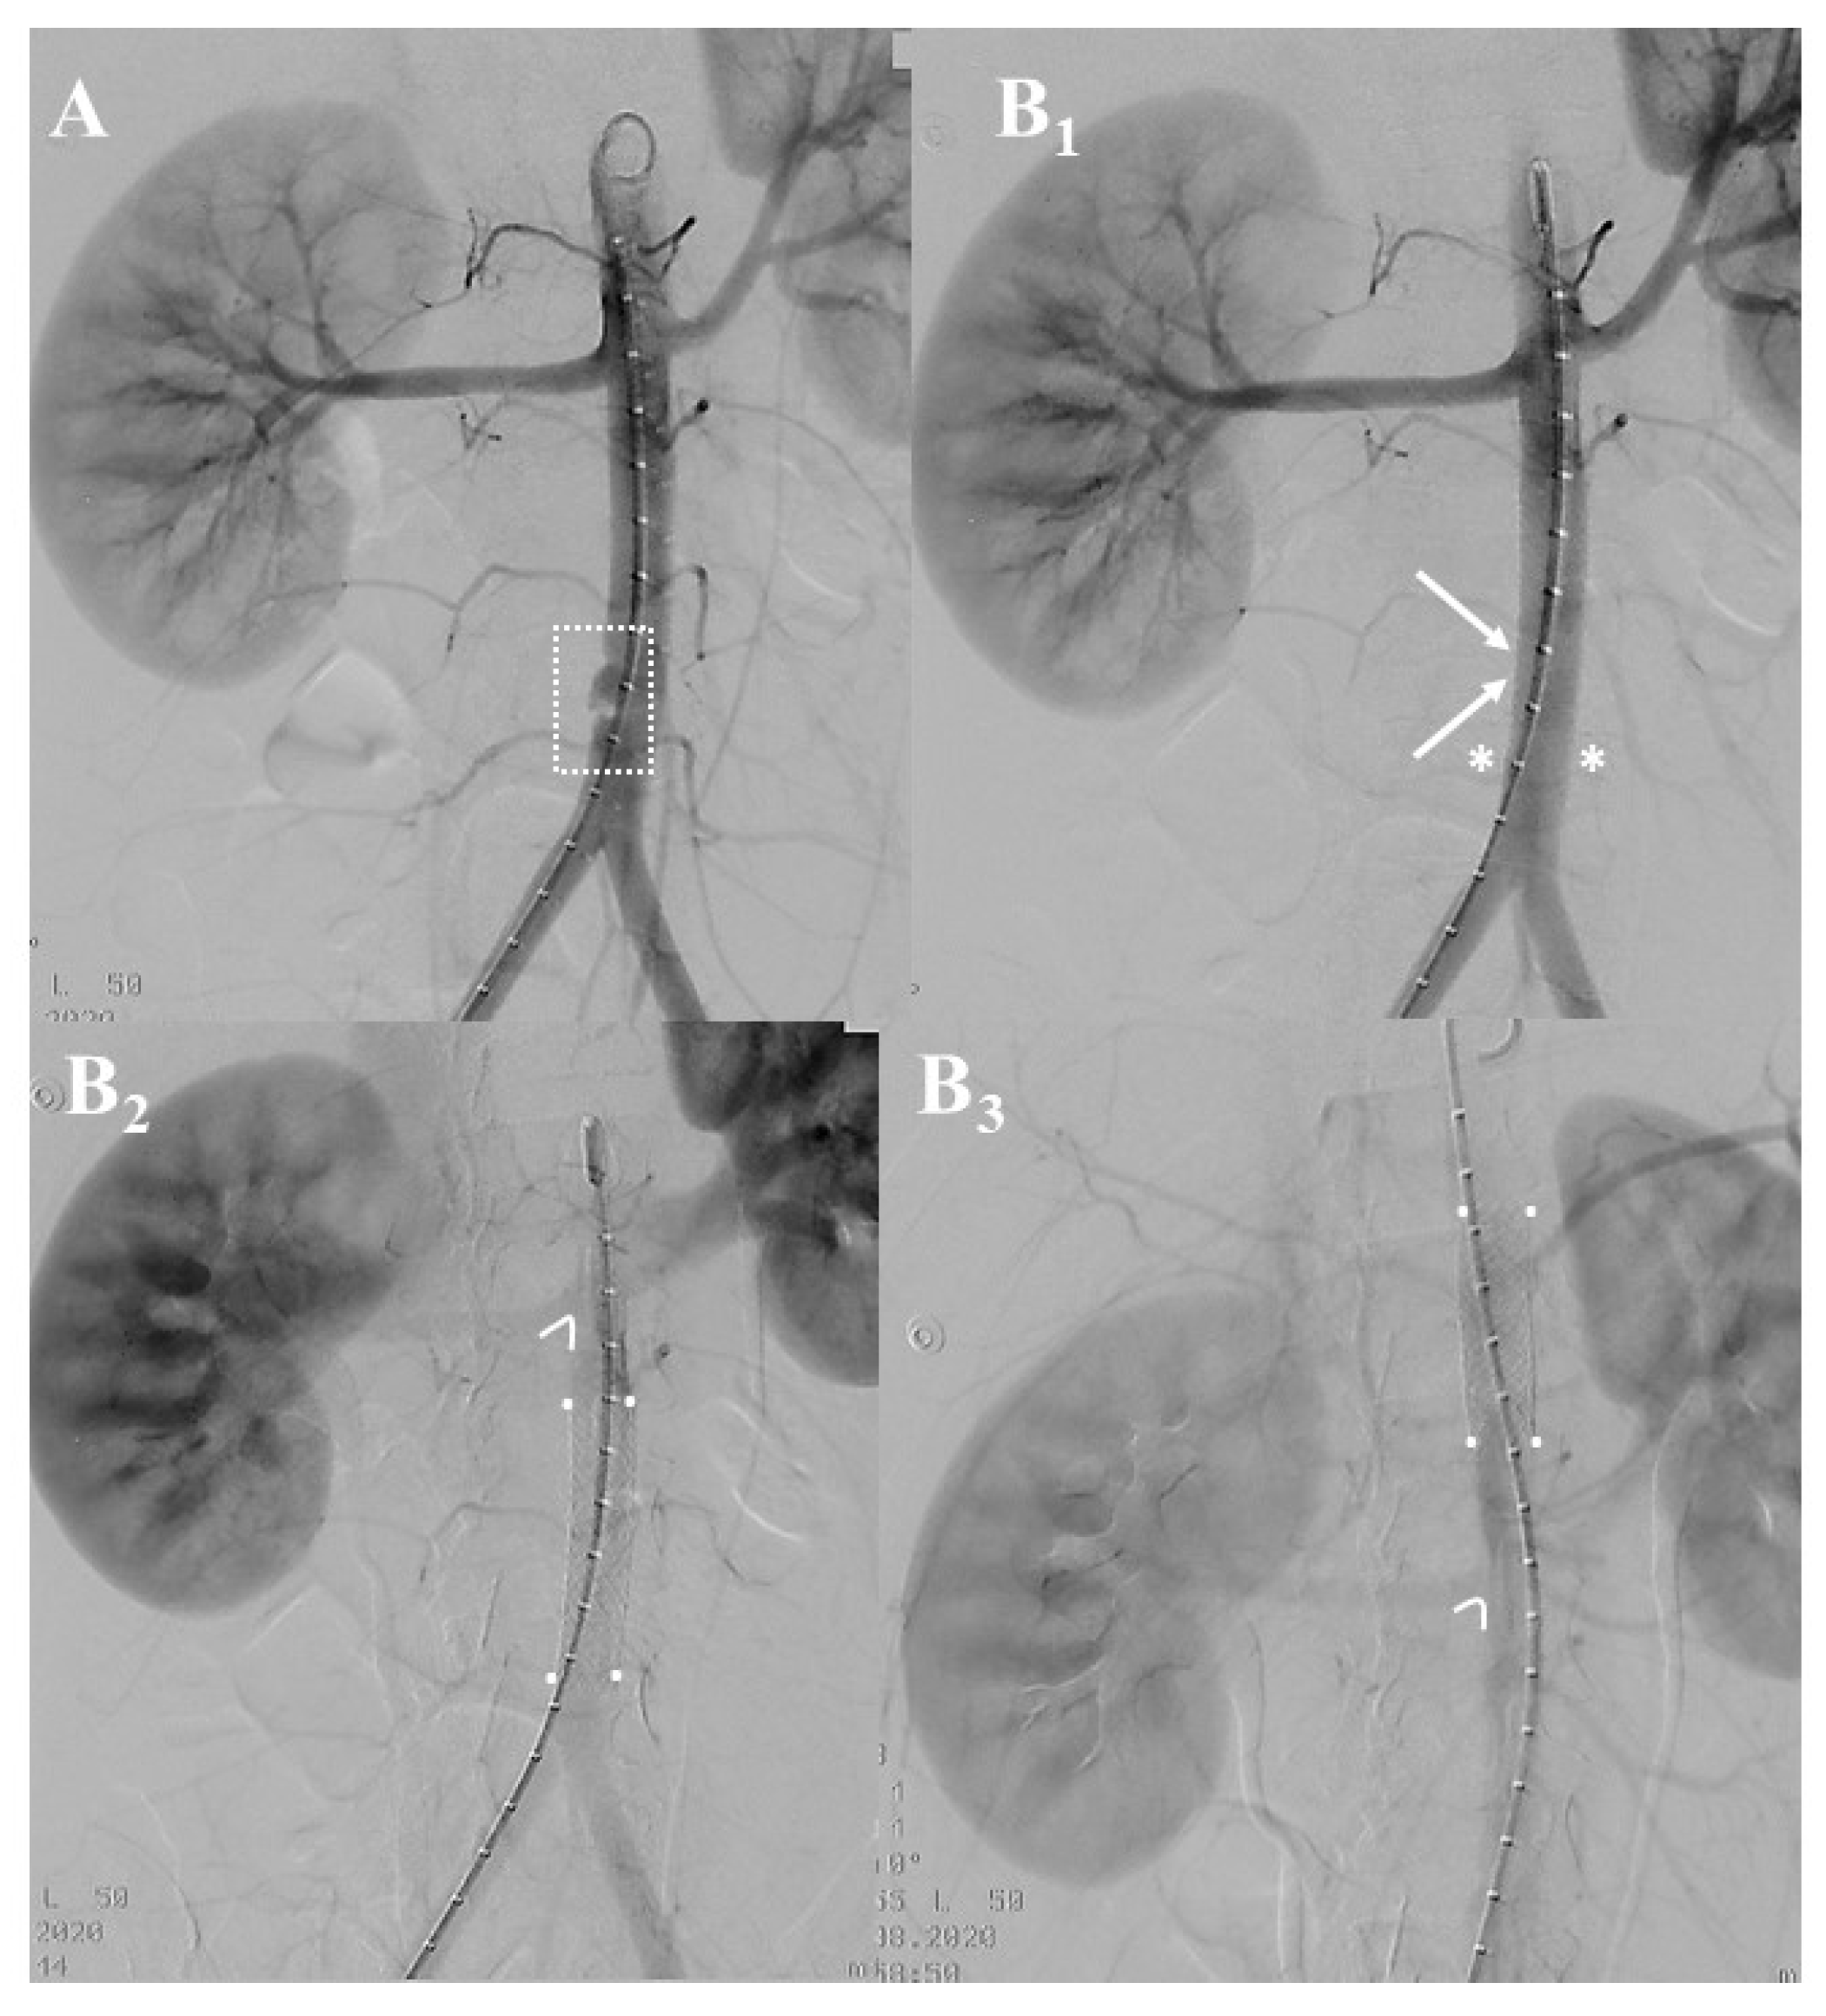

3.3. Institutional Case Report #3—Aortic Injury and Open Surgery for Failed Endovascular Treatment